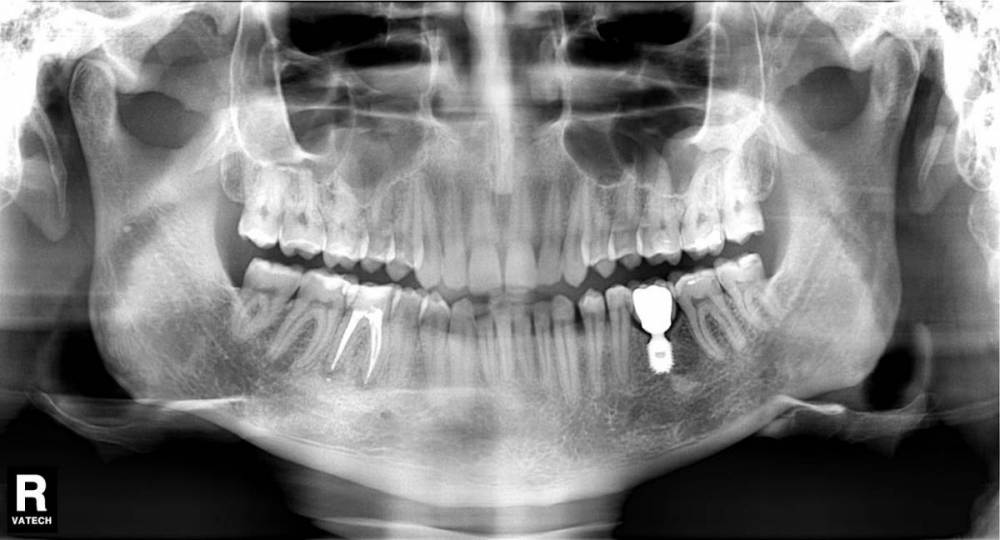

bobrdobr Опубликовано 26 марта, 2021 Поделиться Опубликовано 26 марта, 2021 (изменено) Добрый день, Делаю коронку на 46 зуб. Предложили 2 варианта: металлокерамика на метал. вкладке, 20 т.р. безметалловая керамика на циркониевой вкладке, 40 т.р. Есть причины выбрать вариант 1, а не 2? Эстетика не важна, важны цена/качество/срок службы. На 36 зубе 5 лет имплант с МК коронкой - жалоб нет. 46 зуб депульпирован 10 лет назад, 5 лет назад перелечен из-за периодонтита - успешно. Сейчас начала раскалываться стенка впереди. Показывал паре ортопедов, оба сказали, что разрушения для успеха протезирования не критичны. Спасибо! Изменено 26 марта, 2021 пользователем bobrdobr Ссылка на комментарий